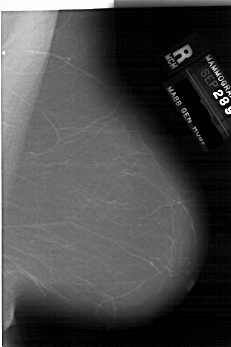

Во время скрининга маммографии используются два вида:

Медиолатеральный косой вид

Краниокаудальный взгляд.